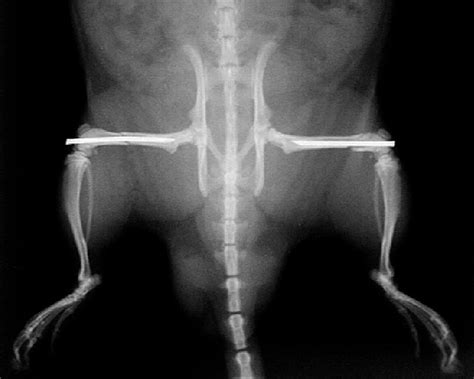

Bilateral Femur Fracture Images

Bilateral femurs, ankle, and left ulna fractures in 20f (c101727).

The treatment can vary based on the location and pattern of the break. Related online courses on physioplus. She sustained no external trauma during the seizure. A femur fracture is an injury to the thigh bone usually caused by trauma. Femoral shaft fractures can also result in major physical impairment due to potential fracture the diagnosis and management of midshaft femur fractures in adults will be reviewed here. *classically this is a transverse fracture in the proximal femur. Most of these cases are unilateral.bilateral simultaneous femur neck fracture is a rare occurrence. Bilateral femurs, ankle, and left ulna fractures in 20f (c101727). Less comminuted fracture nailed first to assess length. Femur fractures are most commonly seen in a traumatic accident. I believe the orthopedic surgeons have a. Simultaneous bilateral fractures of the femoral neck are considered very rare injuries. Hip fractures are one of the most common injuries which present to an orthopaedic surgeon. What's a bilateral femur fracture? Bilateral femur fractures are uncommon injuries and in our study have an incidence of 3.2%. Atypical femur fractures (aff) are associated with bisphosphonate osteoporosis therapy. This case report, in addition to a review of the literature, shows that use of the bisphosphonate class of medications for an.